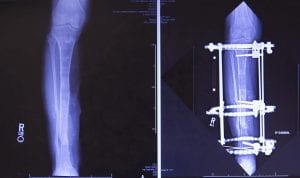

Second, once that healed, Stoneback would cut around the hard outer layer of Judge’s tibia (called a corticotomy) a couple of inches below the knee. Doing so would leave the blood vessels and other tissues inside and outside the calcified bone intact. Then Stoneback would fit Judge’s lower leg with a circular ring fixator to commence the process of bone transport via distraction osteogenesis.

That last bit is a mouthful, but it’s simple enough in concept: with help from erector-set-style hardware (the circular ring fixator) screwed into the tibia above and below the point at which Stoneback cut and again high and low on the tibia to provide stability. Judge would slowly grow another four centimeters (1.57 inches) of shinbone to close the gap the accident had left down low. The plan also involved planting antibiotic beads at the injury site – to make sure the stubborn pseudomonas were truly erased – and also cutting the edges of the damaged shinbone at the injury site so they would come together flush.

It did survive, and by May, it had healed to the point that Stoneback could get to work, installing the ring fixator. For nearly three months, Judge adjusted the ring fixator three times a day, slowly separating the tibia where Stoneback had cut. She and Burnett moved into an apartment near UCH so Stoneback could keep close tabs on her during this critical phase.

By mid-July 2017, the gap at the original wound site had all but closed and the bone transport, as it’s called, complete. Stoneback took bone marrow from Judge’s hip to complete the repair at the injury site (her own body had regrown the four centimeters of bone higher up). The ring fixator, left in place to support her tibia as it healed, came off in November 2017. She started physical therapy.